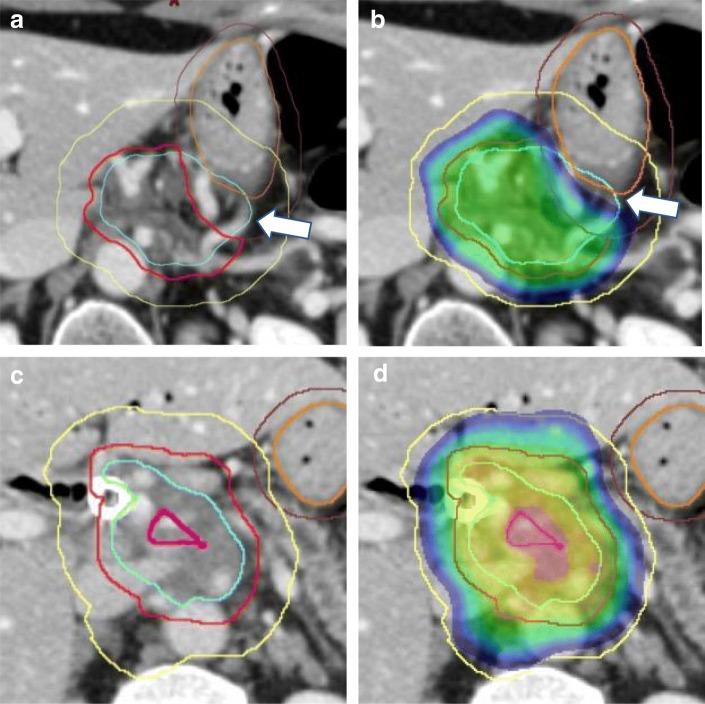

Standard doses of conventionally fractionated radiation have had minimal to no impact on the survival duration of patients with locally advanced unresectable pancreatic cancer (LAPC). The use of low-dose stereotactic body radiation (SBRT) in 3- to 5-fractionshas thus far produced a modest improvement in median survival with minimal toxicity and shorter duration of treatment, but failed to produce a meaningful difference at 2 years and beyond. A much higher biologically effective dose (BED) is likely needed to achieve tumor ablation The challenge is the delivery of ablative doses near the very sensitive gastrointestinal tract. Advanced organ motion management, image guidance, and adaptive planning techniques enable delivery of ablative doses of radiation (> = 100Gy BED) when more protracted hypofractionated regimens or advanced image guidance and adaptive planning are used. This approach has resulted in encouraging improvements in survival in several studies. This review will summarize the evolution of the radiation technique over time from conventional to ablative and describe the practical aspects of delivering ablative doses near the GI tract using cone beam CT image (CBCT) guidance and online adaptive MRI guidance.

标准剂量的常规分割放疗对局部晚期不可切除胰腺癌(LAPC)患者的生存时间几乎没有影响。低剂量立体定向体部放疗(SBRT)在 3-5 次分割中的应用迄今已使中位生存期略有改善,毒性最小,治疗时间缩短,但在 2 年及以后并未产生有意义的差异。需要更高的生物有效剂量(BED)才能实现肿瘤消融。挑战在于在非常敏感的胃肠道附近提供消融剂量。先进的器官运动管理、图像引导和自适应计划技术可在使用更延长的低分割方案或先进的图像引导和自适应计划时提供消融剂量的放疗(> = 100Gy BED)。这种方法已导致几项研究中生存的可喜改善。本综述将总结随着时间的推移,放疗技术从常规到消融的演变,并描述在胃肠道附近使用锥形束 CT 图像(CBCT)引导和在线自适应 MRI 引导来提供消融剂量的实际方面。